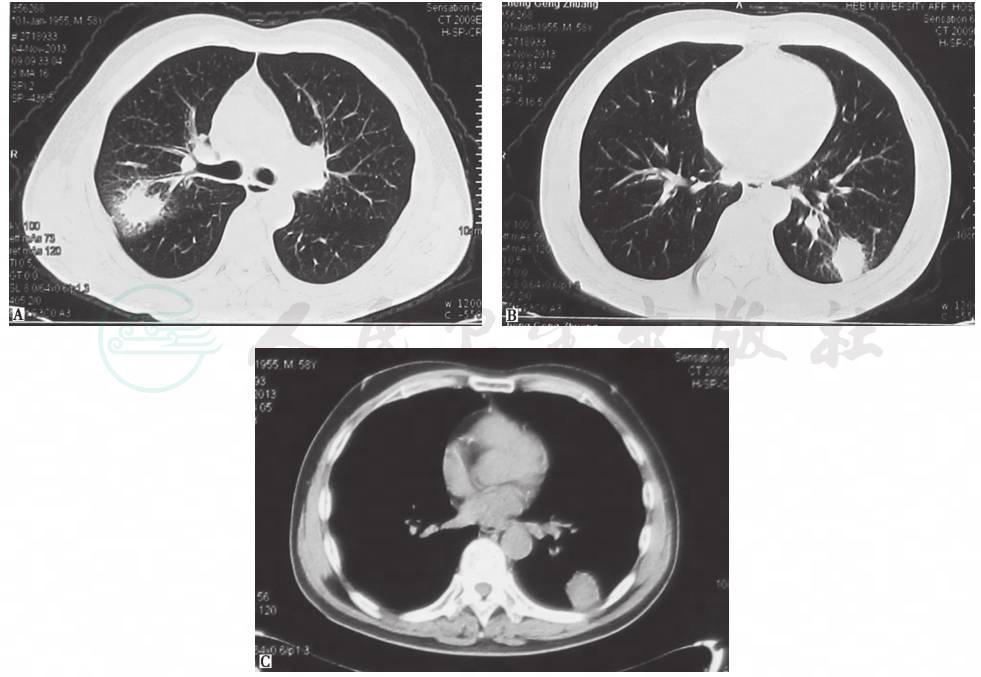

胸部CT示右上叶后段、左肺下叶团块状实变影,周围有磨玻璃影及索条影(图1)。

图1 胸部CT表现(2013-11-04)